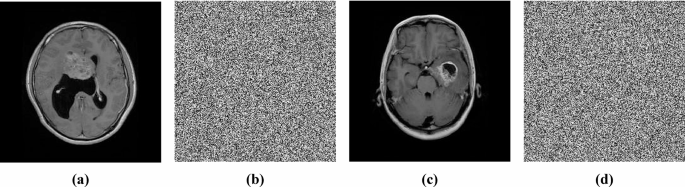

Examples of plain images from the mentioned dataset and their corresponding encrypted images are shown in Fig. 5.

Grayscale images

Although this study focuses on color image encryption, the proposed method can also be used for a single grayscale channel. Some analyses are performed to evaluate the scheme for grayscale images. Figures 12 and 13 illustrate the encryption and decryption methodology for grayscale images, and Fig. 14 shows examples of plain grayscale medical images and their corresponding encrypted images.